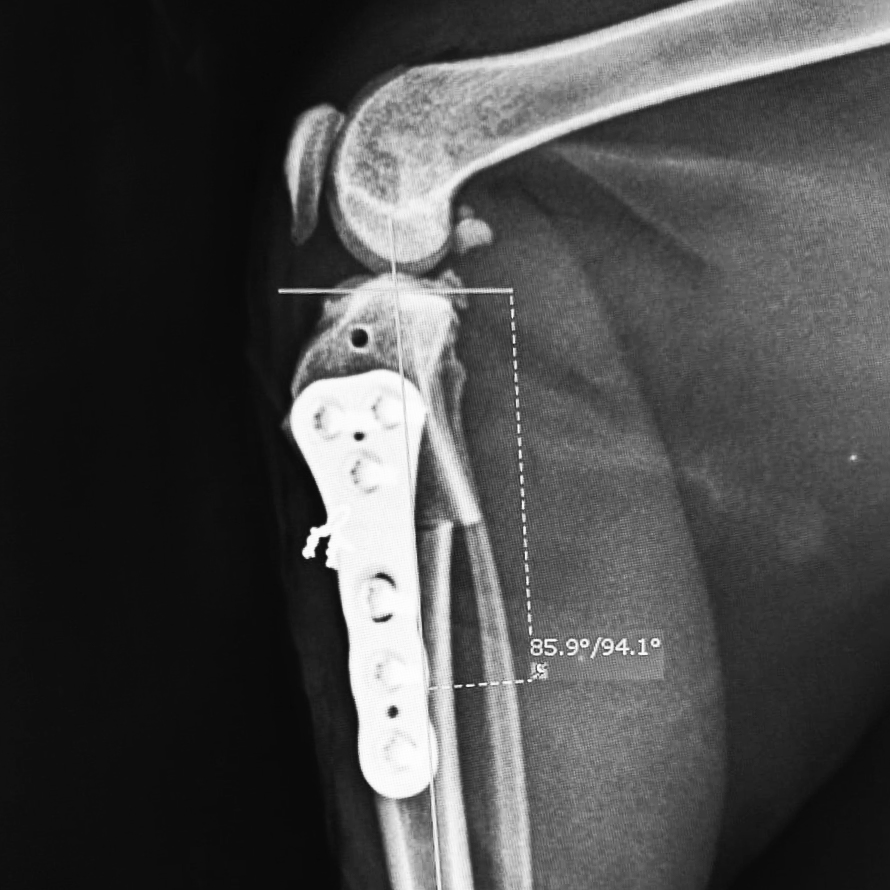

Die Cranial Closing Wedge Osteotomy (CCWO) ist eine etwas in Vergessenheit geratene Technik zur Behandlung von Kreuzbandrissen bei Hunden und Katzen. Ähnlich zur CBLO verändert diese den Winkel des Tibiaplateaus bei gleichzeitigem TTA-Effekt. Neu ist jedoch der der CORA-basierte Ansatz. Die präoperative Planung ist individuell auf die spezifische Anatomie und Gewichtsverteilung des Patienten abgestimmt. Besonders bei steilen Tibiaplateau-Winkeln und jungen Patienten überzeugt die Methode durch ihre geraden, exakten Osteotomien, die außerhalb der Wachstumsfugen verlaufen. Charmant ist außerdem, dass nur gerade Sägeschnitte gemacht werden. Eine oszillierende Säge ist ausreichend.

Von Rita Leibinger gibt es nun speziell anatomisch geformte CCWO-Platten mit dem bewährten LeiLOX System, kompatibel zu den TPLO und CBLO Systemen. Gemeinsame Instrumente und identische Titanschrauben bieten maximale Flexibilität und Effizienz. Die Titan Implantate heben sich durch optimale Biokompatibilität, hohe Stabilität und Langlebigkeit hervor.

Die anatomisch vorkonturierten Platten mit limited contact minimieren die Durchblutungseinschränkungen und unterstützen eine schnellere Heilung. Die multiaxiale Schraubenverriegelung ermöglicht eine Fixierung im 90°-Winkel mit bis zu 12° Abweichung, was eine flexible Platzierung fern von vitalen Strukturen gewährleistet.

Durch ihr anatomisches Design ist die Platte bereits vorkonturiert und liegt damit ideal am Knochen an. Dies erlaubt eine komfortable Handhabung und hohe Stabilität. Die Plattenunterseite ist nur in minimalem Kontakt zum Knochen zur Verbesserung der vaskulären Versorgung.

Die Verriegelungsschrauben können variabel in einem Winkel von 90° ± 12° gesetzt werden. Dies erlaubt es Ihnen, bestimmte Schrauben von kritischen Stellen wegzuwinkeln.